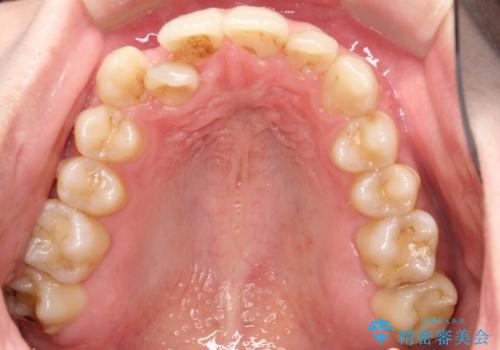

右上の犬歯が外側に飛び出して、二番目の歯が内側に入っている状態でした。

上の奥歯を後方に移動させてスペースを確保して、前歯のガタガタを改善する計画としました。

奥歯を後方に移動することで、歯を抜かずに矯正を終えることができました。